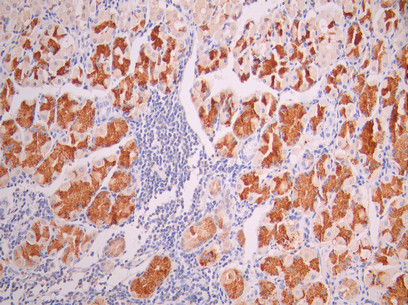

IHC image of CSB-RA015215MA1HU diluted at 1:50 and staining in paraffin-embedded human stomach tissue performed on a Leica BondTM system. After dewaxing and hydration, antigen retrieval was mediated by high pressure in a citrate buffer (pH 6.0). Section was blocked with 10% normal goat serum 30min at RT. Then primary antibody (1% BSA) was incubated at 4°C overnight. The primary is detected by a Goat anti-mouse polymer IgG labeled by HRP and visualized using 0.05% DAB.

Application Recommended Dilution IHC 1:50-1:200 -